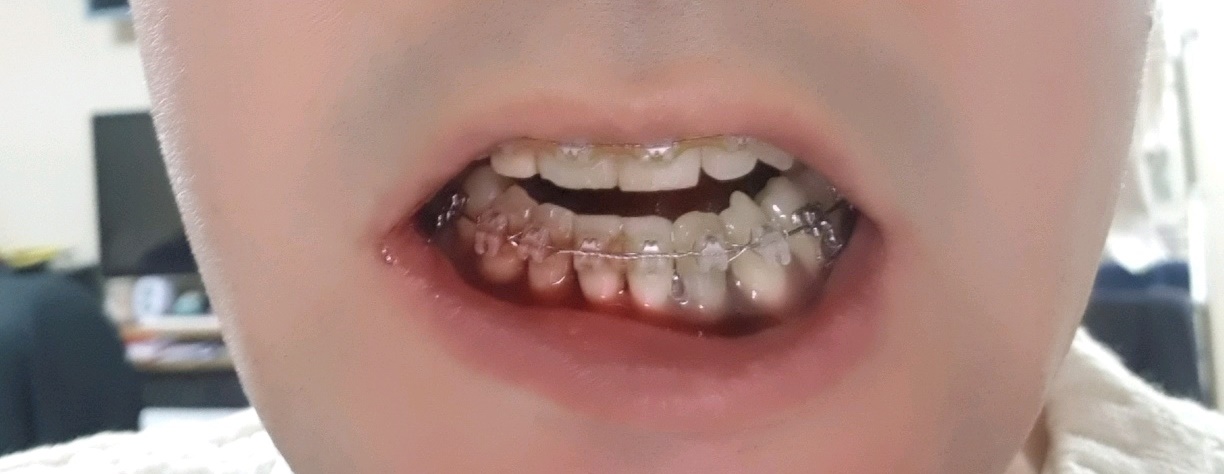

3년전 부정교합 시작하기 전의 내 치아 상태는 지금 생각해 보면 정말 최악?? 이였다..

썩은치아와, 부정교합으로 인해 삐뚤어진 치아들...

여튼~ 그건 그렇고 이제 슬슬 치아교정 마무리가 되어가니

교정때문에 발치했던 치아포함 임플란트를 해야할 날이 다가왔다...